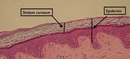

Ciğerde yara veya karaciğer yarası, genellikle karaciğerin iltihaplanması, hasar görmesi veya enfeksiyon sonucunda meydana gelen bir durumdur. Karaciğer, vücudun en büyük iç organlarından biri olup, birçok önemli işlevi vardır. Bu makalede, ciğerde yara belirtileri, nedenleri, tanı yöntemleri ve tedavi seçenekleri ele alınacaktır. Ciğerde Yara Nedenleri Ciğerde yara oluşumuna neden olabilecek birçok faktör bulunmaktadır. Bunlar arasında:

Bu nedenlerin her biri, karaciğerin yapısında ve işlevselliğinde değişikliklere yol açarak yara oluşumunu tetikleyebilir. Ciğerde Yara Belirtileri Ciğerde yara belirtileri, genellikle hastalığın evresine ve ciddiyetine bağlı olarak değişir. Aşağıdaki semptomlar, karaciğer yarası olan bireylerde sıkça gözlemlenebilir:

Belirtilerin varlığı, karaciğerin durumunu anlamak için bir uyarı niteliği taşır ve sağlık uzmanlarına başvurulması gerekmektedir. Tanı Yöntemleri Ciğerde yara teşhisi için farklı tanı yöntemleri kullanılmaktadır. Bu yöntemler arasında:

Bu yöntemler, karaciğerdeki hasarın boyutunu ve nedenini belirlemeye yardımcı olur. Tedavi Seçenekleri Ciğerde yara tedavisi, yaranın nedenine ve ciddiyetine bağlı olarak değişiklik göstermektedir. Genel tedavi seçenekleri şunlardır: